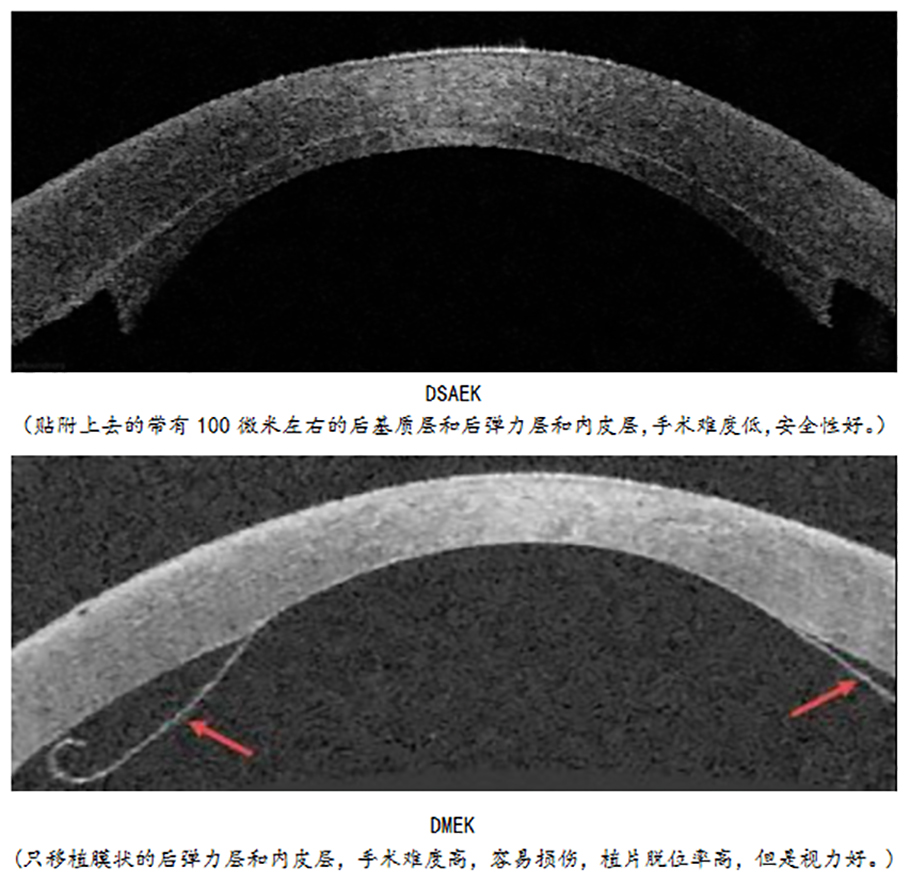

中央厚度仅0.5毫米的角膜分为5层,中间层“角膜基质层”占角膜的90%,而菲薄的角膜后表面包含了“后弹力层”和“内皮细胞层-使角膜保持透明的最重要一层细胞”。像余女士这样仅角膜后表面出现问题的患者在角膜病患中不占少数。传统的穿透性角膜移植手术需要切除患者的全层角膜,包括前面的健康角膜基质,这显然不是理想的手术方式。因而在过去的20年,全球角膜病专家不断探索高选择性的内皮移植手术,目前主流的手术是后弹力层剥除自动板层刀角膜内皮移植(DSAEK)和最新的术中仅移植后弹力层和内皮细胞(DMEK)。DSAEK手术简便,但视力恢复不是很理想,最新的DMEK手术从解剖学角度完美恢复了角膜组织的正常结构,可更好更快恢复视力,而且术后排斥反应率非常低,近年来在全世界范围内得到广泛关注。但是,DMEK对捐献者的年龄和内皮细胞数量有很高的要求,供体制备过程中内皮细胞容易损伤,以及植入内皮片后在前房的展开和贴附很困难,容易脱位,手术医师学习曲线很长,目前我国尚无大规模开展DMEK的报道。

为了克服DMEK的这些缺点,陈蔚教授在大量开展DSAEK和深板层角膜移植的经验基础上,为该患者实施了自动板层刀辅助的后弹力层前膜内皮移植术(PDAEK)。PDAEK其实是一种设计非常巧妙的DSAEK和DMEK手术的杂交技术,角膜植片中央6.5毫米和DMEK一样只剩下后弹力层前膜和内皮,周边1毫米左右则和DSAEK一样有少许厚度,这样既避免了DSAEK仍带有部分基质可能导致视觉质量下降和远视偏移的局限,又克服了DMEK可能的内皮损伤和手术难度大时间长的缺点,大大提高了DMEK手术的安全性和可操作性。